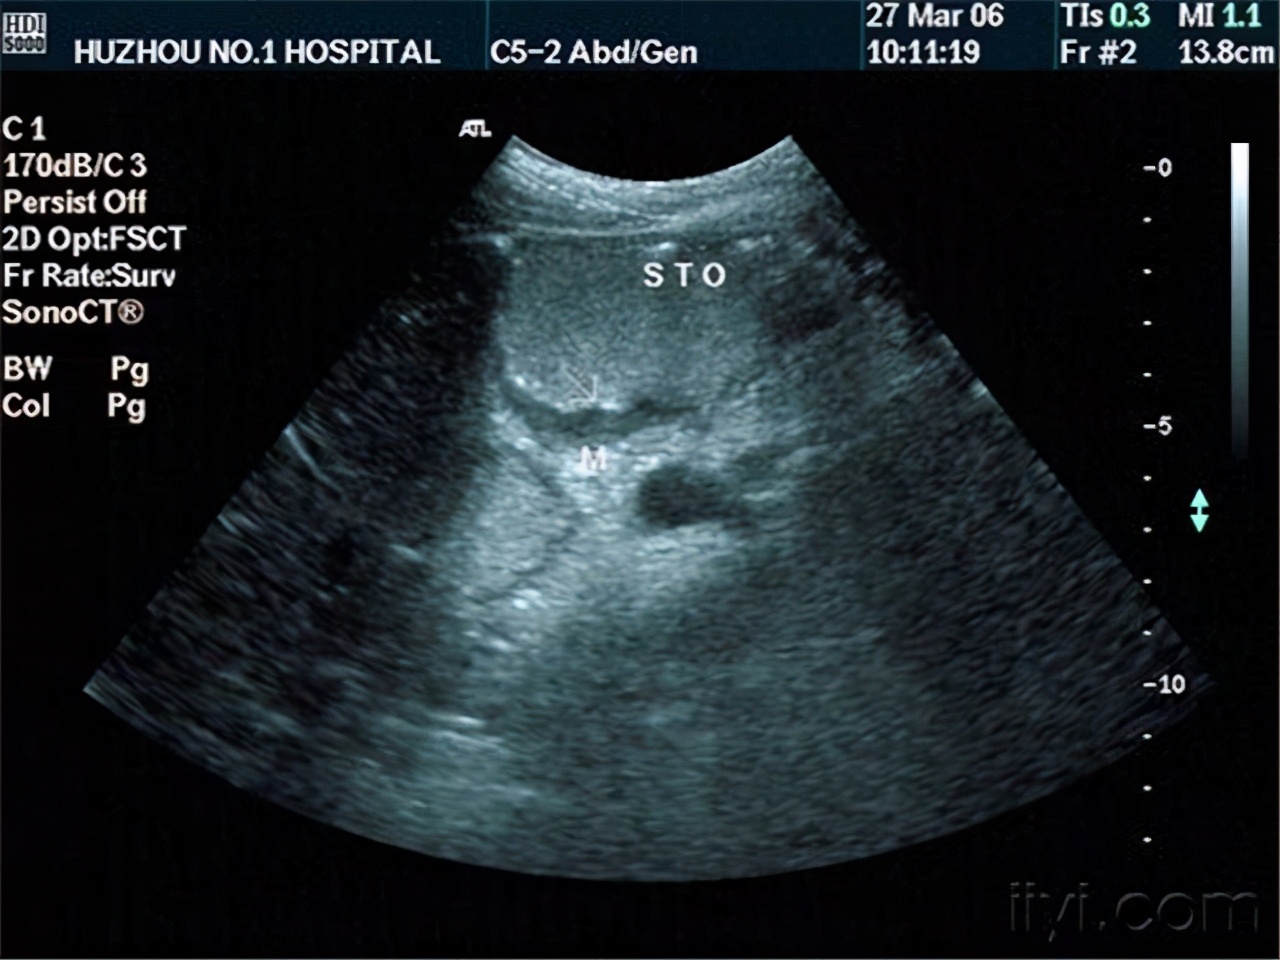

所谓的彩超,是一种医疗器械 ,这种检查设备通常用于医院或者研究室等场所,它由探头、超声波发射/接收电器、信号处理、图像显示等其余部分组成。

这种医疗器械会测量和采集血流运动信息,进一步形成超声影像 ,医生看得懂超声影像,并且根据影像呈现的信息来判断病人当前的病情如何。

彩超在腹腔脏器检查中非常有用,熊先生患上了肝癌,所以可以用这种医疗器械进行治疗。 肝癌可以分为转移性肝癌和原发性肝癌 ,而彩超针对的是原发性肝癌。

有相关的学者进行这个项目的研究,他将2016年到2018年这个时间段内的92例早期肝癌患者通过扫描后得到的数据,包括肝癌数目、形态、位置、边缘、管腔情况等因素逐一记录,然后用SPSS26.0软件处理, 得到的结论是原发性肝癌周围血流较为丰富,其中肝的形状是星点状、短节状分布。

多亏有了彩超检查,才能够发现肝癌此刻的形态,根据这些形态可采用相关的治疗方法,加大对患者的治疗效用。

早期若是给肝癌患者提供彩超诊断,那么可以在一定呈上提高诊断的准确性,并且能够明确病变部位下的留学速度、位置、大小等等,帮助医生做进一步分析和判断,安全性也更高。